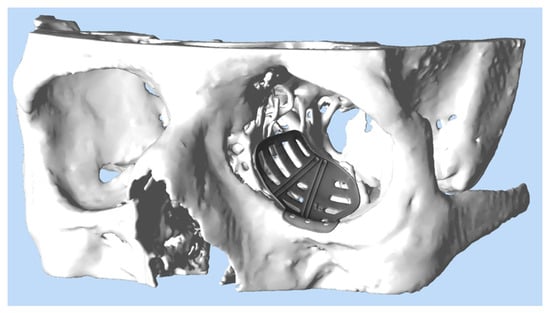

The radiological data (CT scan, minimum 1 mm axial layer thickness) were obtained and after digitally segmenting and mirroring the healthy orbit to the fractures site (iPlan CMF 3.0.5, Brainlab, Munich, Germany), a patient-specific implant was designed (see Figure 2). The decision for the medial wall reconstruction was strongly made in the coronal view. The border was pointed with land marks. Additionally, the posterior bulge was analyzed in the axial view and virtually reconstructed. After transmission of the data to the company KLS-Martin (Tuttlingen, Germany) or Synthes (Umkirch, Germany), production took place in a selective laser melting process using Ti-Alloy Ti6Al4V Grade IV. The PSIs had a thickness of 0.3 mm with a 0.5 mm thick cord on the circumference. The whole work flow from data obtainment to delivery of the ready-to-use product took between 8 to 10 working days.

Figure 2.

Virtual design of a PSI for reconstruction of the left orbit. The PSI (grey) has been provided with trajectory lines for intraoperative navigation and drain grooves to ensure postoperative drainage.